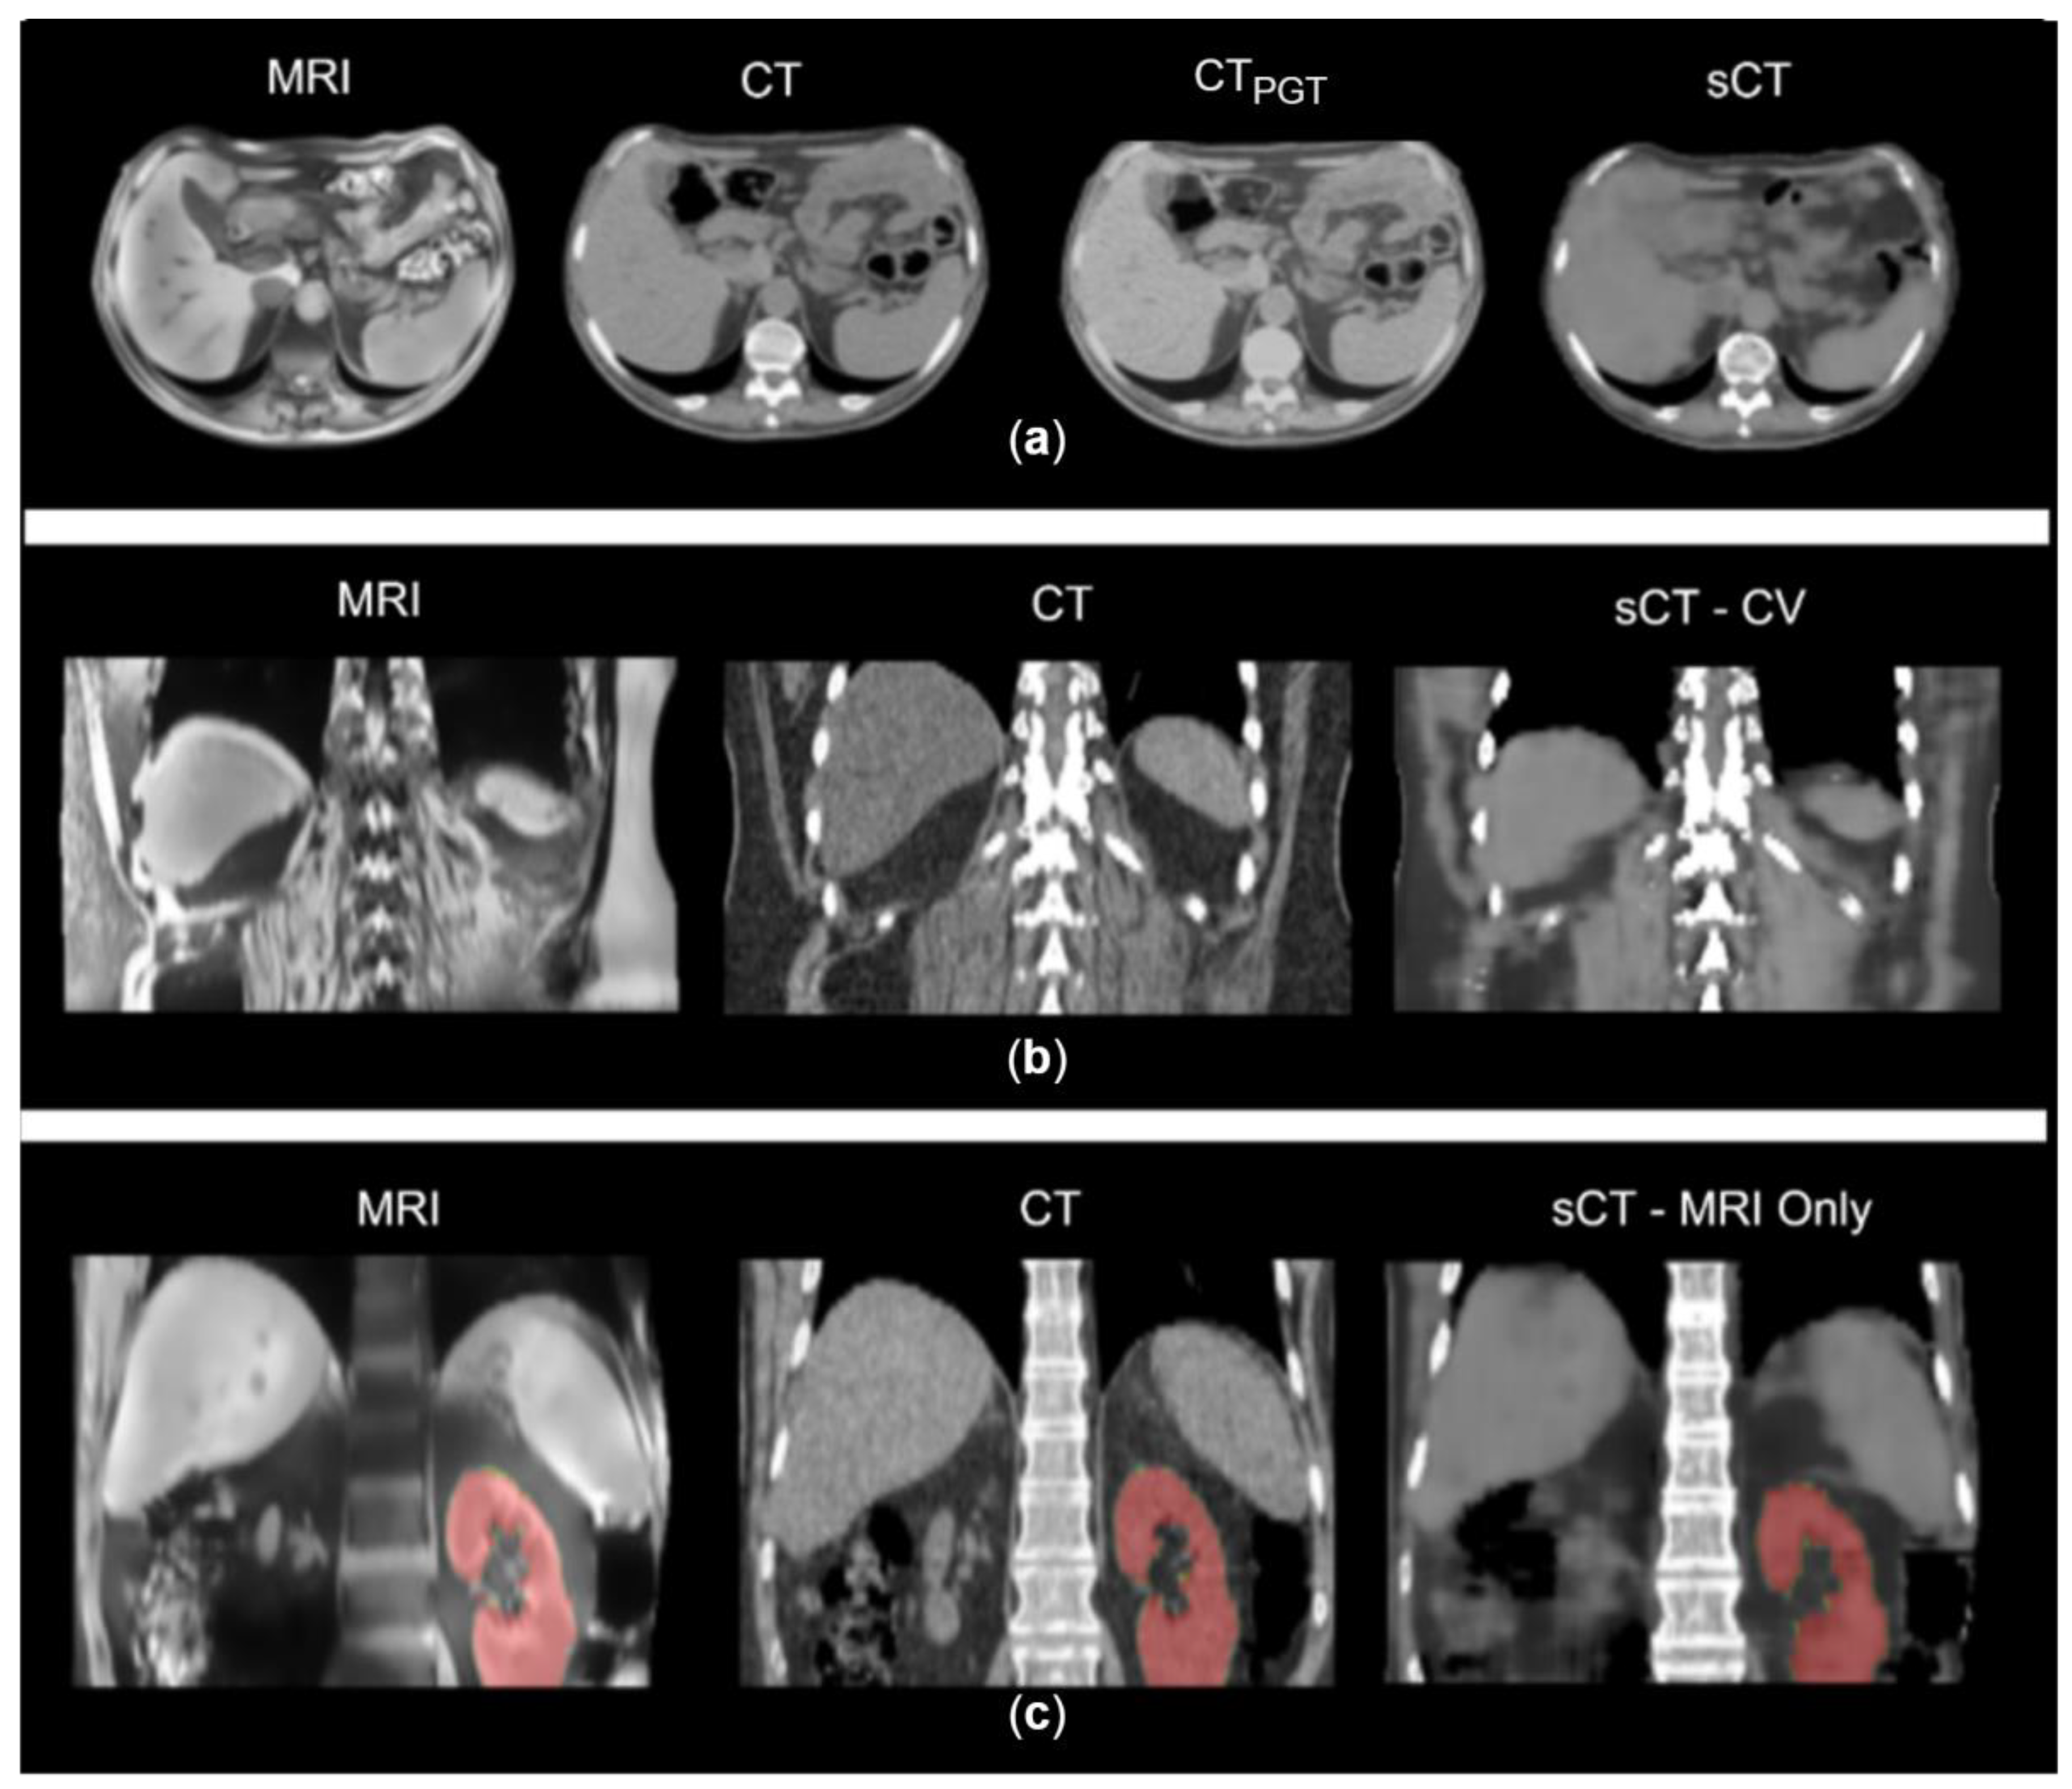

2. Materials and Methods

2.4. Experiments

3. Results